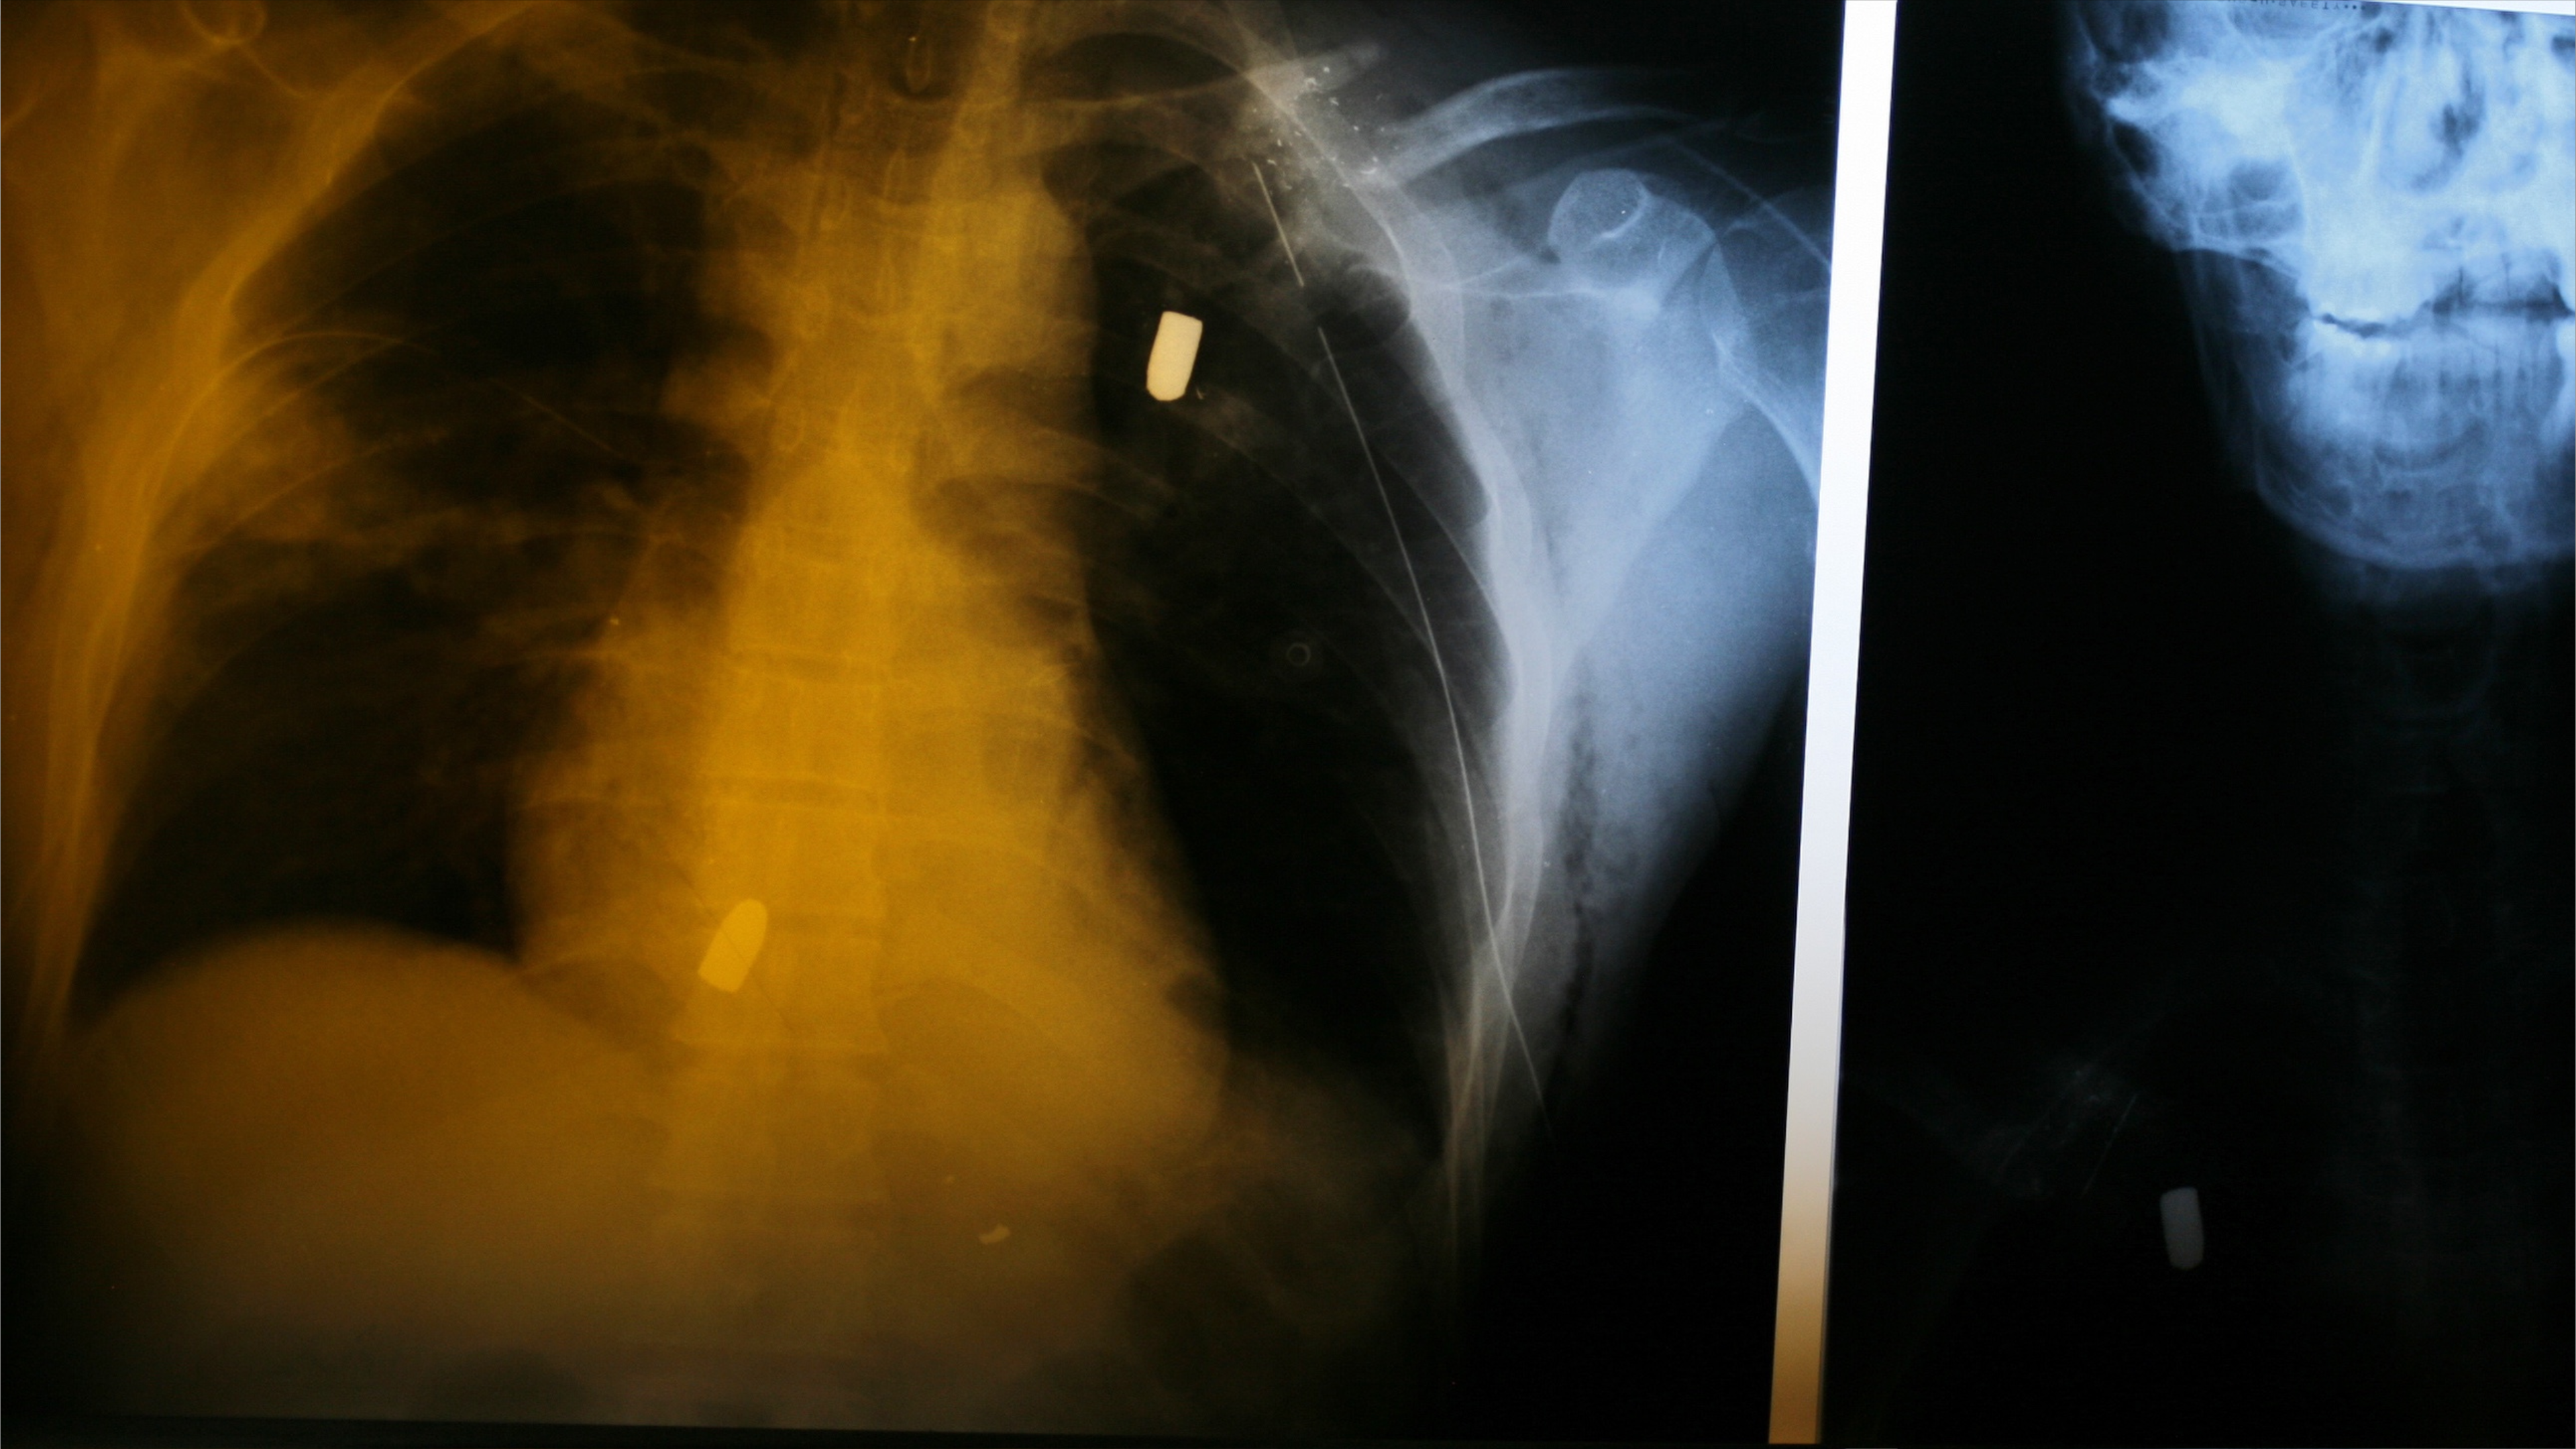

تشمل الصور الطبية التي اطّلعت عليها الغارديان أشعة سينية وصور طبقي محوري لمرضى وصلوا إلى مستشفى واحد خلال ساعات قليلة من ليلة قمع الاحتجاجات.

وتُظهر عشرات النقاط المعدنية الصغيرة المنتشرة داخل الرأس والوجه والصدر، وهي كريات معدنية تُعرف باسم "birdshot" تُطلق من بنادق خرطوش.

في حالة شابة في أوائل العشرينات، تظهر الأشعة نقاطا بيضاء منتشرة عبر العينين وعظام الوجه وحتى قرب الدماغ، وتمثل كل نقطة كرة معدنية قطرها بين 2 و5 مليمترات، وقد تسببت بفقدان عين واحدة على الأقل وربما كلتا العينين.

يشير التحليل إلى أن نحو 29 مريضا في الملفات التي جرى فحصها أصيبوا بطلقات خرطوش في الوجه تحديدا. قال خبراء الأشعة والصدمات إن هذا النوع من الإصابات يؤدي غالبا إلى العمى والتشوه الدائم وأحيانا أضرار دماغية وإعاقات مستمرة.

أظهرت بعض الصور رصاصات كبيرة العيار مستقرة داخل الجمجمة أو الرقبة أو قرب العمود الفقري، مع مسارات تدمير واضحة في العظام والأنسجة.